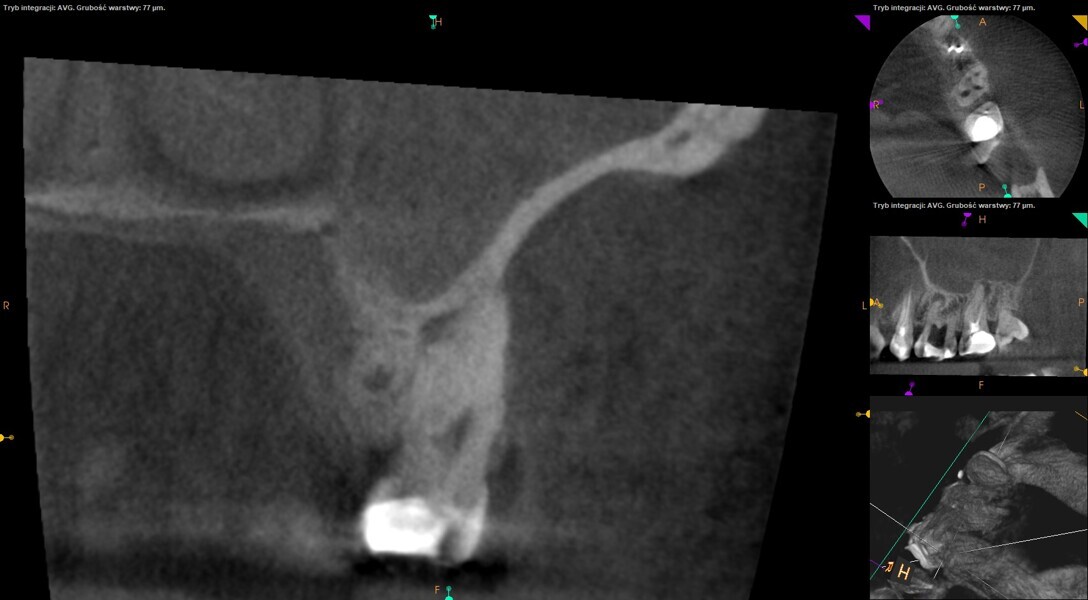

At the second appointment, the temporary restorations were removed, and the chlorhexidine was washed out with sterile water and EDTA. After opening the orifice of the MB2 canal in the first molar, the operator was not able to reach patency in the canal. Therefore, the isthmus between the MB1 and MB2 orifices was opened with diamond-coated ultrasonic tips. Finally, patency was reached. Shaping the MB2 canal in the second molar was possible only to the place of the junction with the MB1 canal. The CBCT imaging had revealed previously that the MB2 canal should have its own lumen in the apical third, but the place of the junction was below the curvature. The possibility of locating this space without damaging the root was very poor. At this stage, the LPE enhanced irrigation protocol was performed again. After performing of the irrigation protocol, the apical preparation was performed for all the canals. The final irrigation protocol was performed with 5 minutes of constant flow of 5.25% NaClO for 2 minutes, alternating with 17% EDTA for 30 seconds, with 5.25% NaClO for 30 seconds and 17% EDTA for 30 seconds, and irrigation with 5.25% NaClO for 5 minutes. All the irrigants were activated with an EDDY sonic tip (VDW). After performing the periapical radiographs, a CBCT scan was performed to confirm the separate path of the sealer that filled previously unprepared spaces of the MB2 canals in both teeth. In both cases, it was clearly visible on the CBCT image that all the previously unprepared spaces were filled with the obturation material.

A 25-year-old female patient presented to the office owing to constant pain related to the mandibular left first molar. Pulp necrosis was diagnosed. After the emergency appointment, the patient was referred for complete treatment. The tooth was treated in the same manner as described in the previous paragraphs. After creation of the access cavity, the orifices were located. In the root chamber, the orifices of the MB, mesiolingual, DB, distomesial and distolingual canals were present. After pre-flaring and preparation of the middle third, the LPE enhanced irrigation protocol with the SkyPulse laser was performed. After the irrigation protocol in the mesial root, the irrigants started to flow between lingual and buccal canals. Such an observation suggested to the operator that some space in the isthmus had been created. It is worth mentioning that at this stage apical enlargement was not performed. Final preparation of all five canals was performed with the reciprocating file, and the final irrigation protocol was performed as in the previous case. The radiograph clearly revealed that the isthmus space was filled with the sealer. The radiograph and CBCT image revealed that there were four portals of exit in the mesial root.

A 35-year-old female patient was referred to the office owing to the lack of patency in the pulp chamber. The periapical radiograph and CBCT image confirmed that the pulp chamber was completely calcified. The calcification of the pulp chamber was removed with diamond-coated ultrasonic tips. After removing the calcification, four orifices were located and shaped in the sequence described previously. The LPE enhanced irrigation protocol with the SkyPulse laser was performed. In this case, the MB2 canal joined the MB1 canal approximately 4 mm before the apex and was shaped only to this length. Apical preparation and irrigation were performed as described previously. The periapical radiograph revealed that the MB2 canal had a separate apical part, which was cleaned with the irrigants and filled with the sealer, and that the palatal canal had two portals of exit.